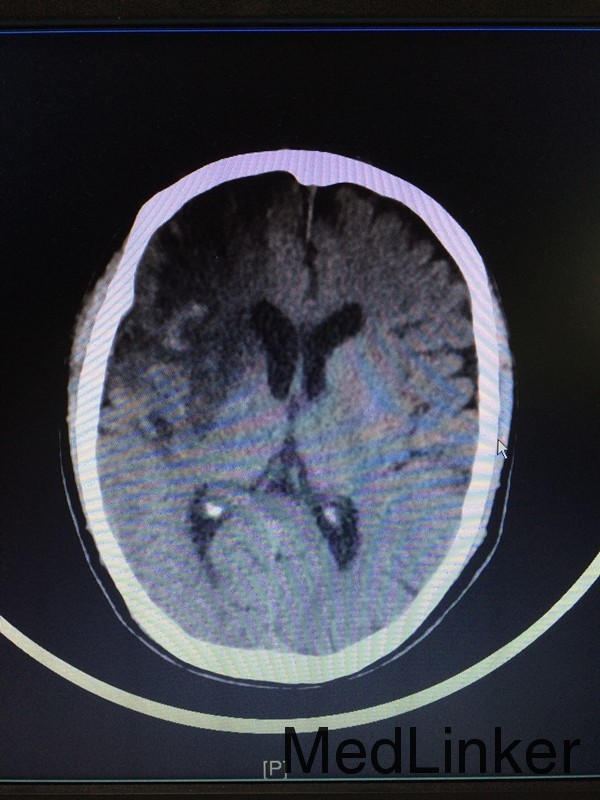

主诉:左侧肢体乏力28天 病史:患者60岁男性,于入院前28天无明显诱因出现左侧肢体乏力,伴言语不清,表现为行走不稳、神志模糊,较烦躁,无头痛、头晕、恶心呕吐等,于当地医院行头颅CT提示:大脑中动脉高密度影。患者第二天出现头痛伴呕吐,急查头颅CT提示:大面积脑梗。

查体:左侧上肢2级,下肢2级,右侧肢体肌力正常 辅助检查:查头颅CTA提示:右侧额叶及岛叶(包括基底节)脑梗塞,轻度脑萎缩,CTA未见明显异常

诊断:右侧额叶及岛叶大面积脑梗塞 治疗:予活血化瘀、改善血管痉挛、脱水降颅压等治疗,并申请康复、高压氧等治疗。

随访:患者病情缓解出院 讨论:患者60岁男性,突发大面积脑梗塞,可能是由脑动脉主干阻塞所致,CT呈现大片状低密度阴影,多为脑叶或跨脑叶分布,脑组织损害范围较大,临床上除表现脑梗塞的一般症状外,还伴有意识障碍及颅内压增高。不排除为体循环的血栓掉落至大脑动脉引起。